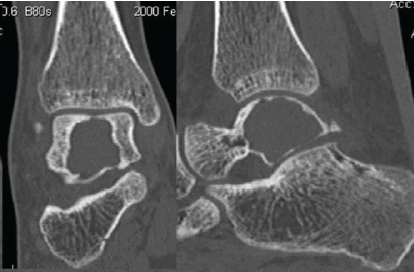

Aneurysmal Bone Cyst of Talus: A Case Report

Segla Pascal Chigblo , Ireti Fiacre Tidjani , Armel Ayaovi Hadonou , Romulus Takin , Fifonsi Odry Agbessi , Aristote Akue Hans-Moevi

………………………………p.125-129